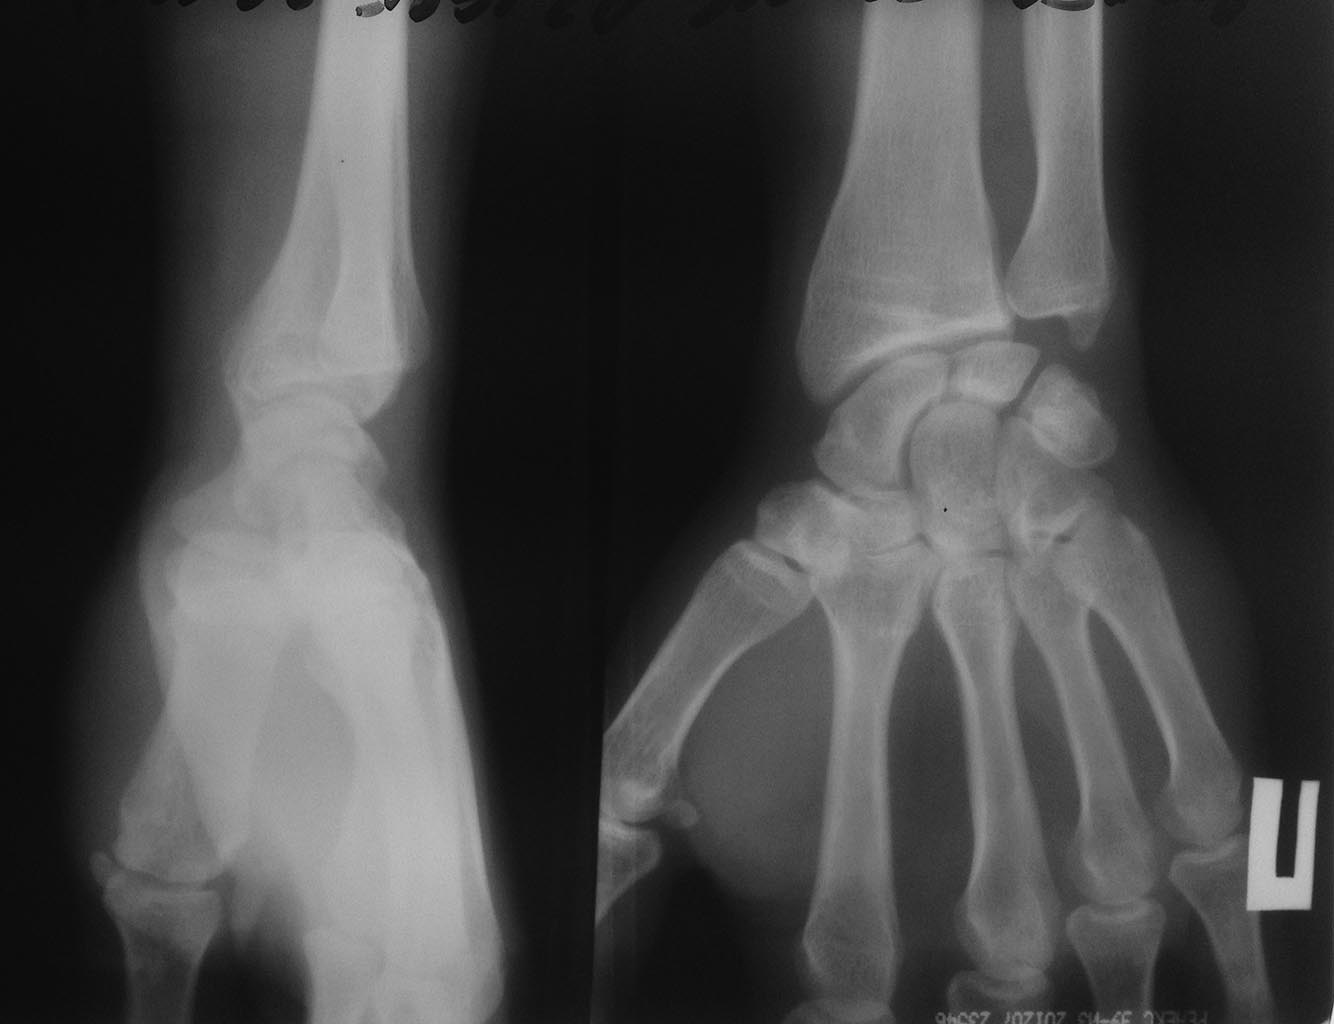

мужчина 32 лет беспокоят боли в правом лучезапястном суставе.

6 месяцев назад появились боли при движение в правом лучезапястном

суставе при физических нагрузках( отжимания) постепенно боли усилились.

Боль локализована в проекции шиловидного отростка локтевой кости, в

покое боли нет. на данный момент движения резко ограничены.

Я третий травматолог к которому он обратился. на свежем снимке похоже

импрессия трехгранной кости?? Направлен на МРТ. Что может быть? Как

лечить? блокаду гормоном не предлагать)